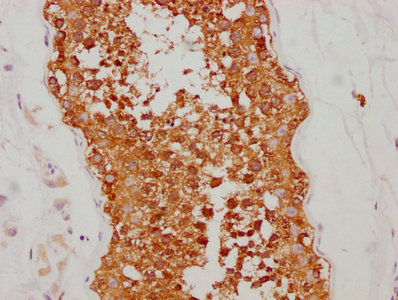

IHC image of CSB-RA011087A2HU diluted at 1:190 and staining in paraffin-embedded human testis tissue performed on a Leica BondTM system. After dewaxing and hydration, antigen retrieval was mediated by high pressure in a citrate buffer (pH 6.0). Section was blocked with 10% normal goat serum 30min at RT. Then primary antibody (1% BSA) was incubated at 4℃ overnight. The primary is detected by a biotinylated secondary antibody and visualized using an HRP conjugated SP system.